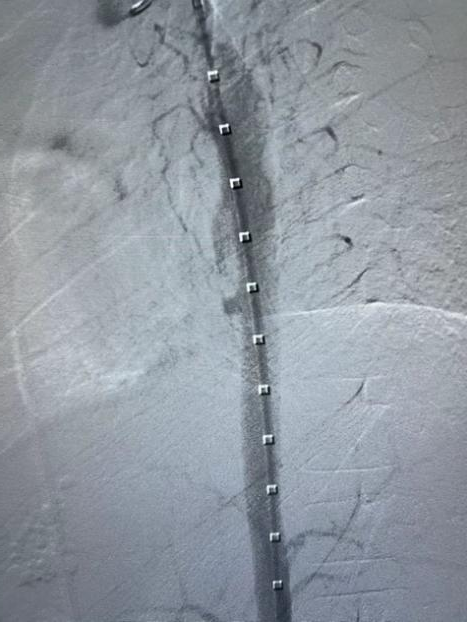

2.根据术前测量患者降动脉9.2mm,选择11*59 mm Gore VBX 球扩覆膜支架,准确定位于后采用球囊扩张,将球囊充盈压到10 atm,将支架扩张至11mm。

3.支架释放后造影提示胸降主动脉局部假性动脉瘤和主动脉食管瘘消失,支架与主动脉贴附良好。

gore医疗怎么样How I Do It | 张雷杨教授团队:Gore VBX用于儿童主动脉食管瘘治疗一例分享_https://www.jmylbn.com_新闻资讯_第5张